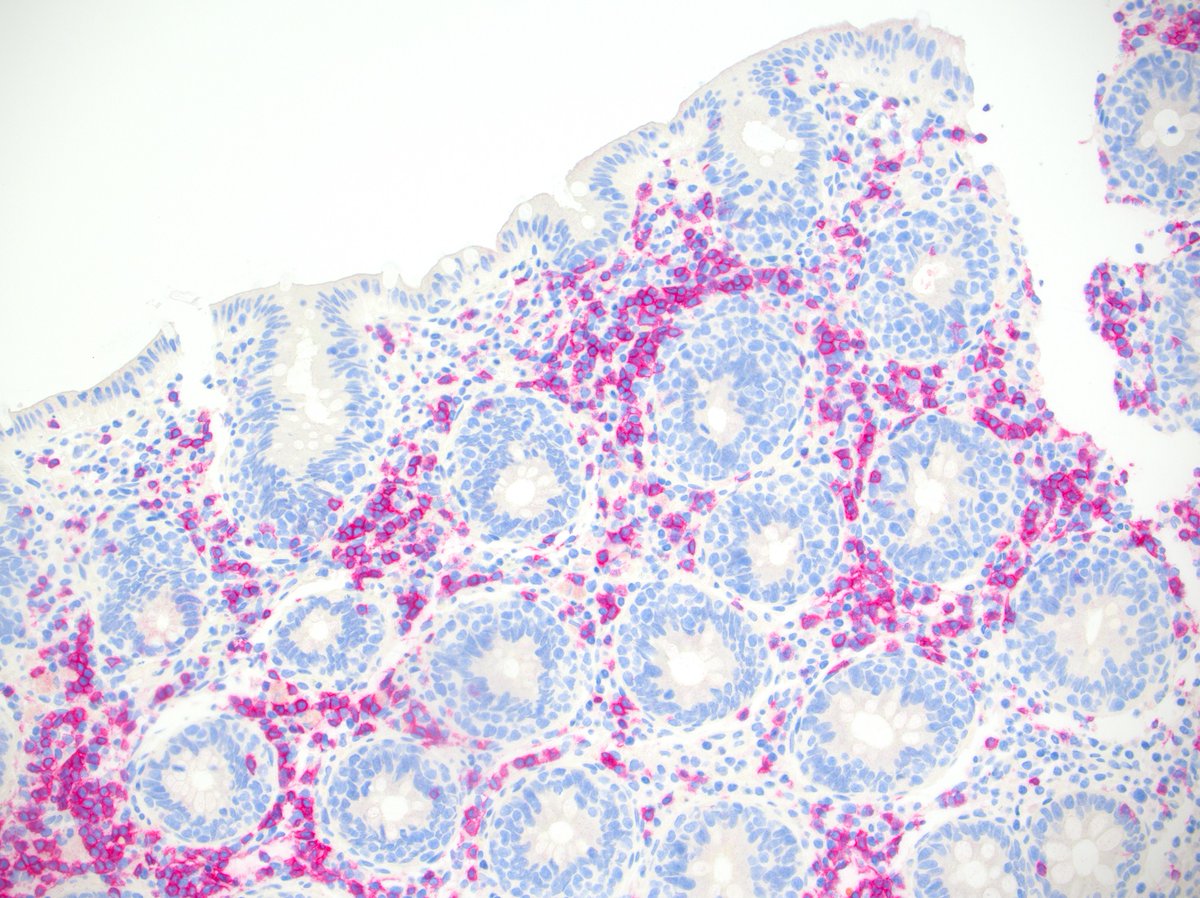

@goziemnweke @AmyHDeekenMD Acid Fuchsine Orange G - one of our favorites for renal pathology because it highlights connective tissue in blue and fibrin in bright red.